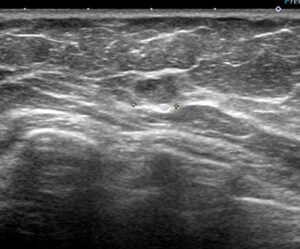

これは「線維腺腫かなー」と思い生検したのですが(コラム526参照)、実際には「癌」でした。

このような経験があるから

こんな「いかにも」線維腺腫だろ?の所見に対してもCELEROするのです。

病理結果は、「こちらは」画像通り「線維腺腫」でした。